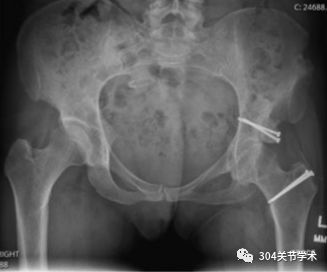

本研究旨在明确关节部分切开联合切开复位内固定术治疗儿童股骨颈骨折是否可降低股骨头骨骺血供破坏的风险。自1989年2月至1994年2月,共纳入13例骨骼发育未成熟的患儿,均接受关节部分切开、清理关节囊内血肿,同时结合切开复位内固定术治疗。其中男3例、女10例;年龄5岁至16岁;骨折原因包括11例交通事故、1例高处坠落以及1例交通事故合并坠落伤。

通过髋关节核磁及其他影像学检查评估术后是否发生股骨头骨骺坏死。患者随访时间为2年至5.5年,平均2年8月。截止末次随访,根据Ratliff 评价标准,12例患者获优良效果,另1例患者获一般效果。无股骨头骨骺坏死、髋内翻、骨折不愈合或骨骺早闭发生。该结果证实了关节切开清理血肿可能会降低儿童股骨颈骨折切开复位内固定术后股骨头骨骺缺血坏死的风险。

典型病例:6岁女,A、B显示III型移位型股骨颈骨折,移位程度占30%-40%;C 伤后48h内,行关节切开血肿清理,同时行切开复位克氏针固定术;D术后41月,骨折愈合无并发症发生。